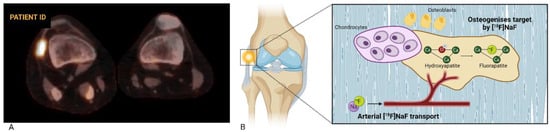

As recommended by the European Association of Nuclear Medicine (EANM), a static whole-body [18F]NaF PET scan can be performed 30–45 min after injection to visualize tracer distribution, but extending the uptake time can improve image quality when assessing the extremities []. The acquisition time is dependent on the injected dose (determined by body weight, ranging from 1.5 to 3.7 MBq/kg), uptake time, patient habitus, PET camera, and acquisition parameters, typically ranging from 1 to 5 min per bed position [,]. Because uptake of [18F]NaF is dependent on hydroxyapatite crystal accessibility and bone blood flow, a [18F]NaF PET scan is a marker for local bone metabolism. Consequently, normal bone turnover is also detected by [18F]NaF PET, albeit at a significantly lower rate compared to processes with increased bone turnover, such as growth plate development, fracture healing or certain bone diseases [,]. Although [18F]NaF uptake generally cannot discriminate among different disorders, the spatial pattern of tracer accumulation can be indicative for specific pathophysiological processes []. Figure 1A shows a fused [18F]NaF PET/CT axial cross section of the right and left knee of a patient with FOP. Increased tracer uptake can be seen in the lateral collateral ligament of the right knee, with no tracer uptake on the contralateral side. Figure 1B shows a schematic overview of the corresponding pharmacokinetics of [18F]NaF, demonstrating the pathophysiological process visualized by [18F]NaF PET scanning.

Figure 1.

(A): Fused axial [18F]NaF PET/CT of the right and left knee of a patient with FOP. Tracer uptake appears as orange-to-white, with white indicating a higher metabolic activity. In the right knee, a lesion with increased focal uptake in the lateral collateral ligament is apparent, while no increased uptake is seen in the left knee. (B): A schematic overview of [18F]NaF uptake incorporation. Chondrocytes create a cartilage matrix, in which adjacent osteoblasts secrete extracellular bone matrix and regulate the mineralization of hydroxyapatite crystals. After intravenous injection, [18F]NaF travels through plasma to areas of bone metabolism. Ionic substitution then results in the replacement of an OH-group by [18F] in hydroxyapatite forming fluoroapatite.